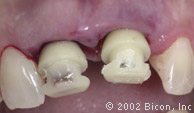

Установка двух 5.0mm x 4.0mm Stealth Shouldered Abutment

Stealth One-Piece Acrylic Sleeves

Изготовление временной конструкции по шаблону

Использование самотвердеющей пластмассы для изготовления временной конструкции

Подготовка для установки временной конструкции

Установка временной конструкции